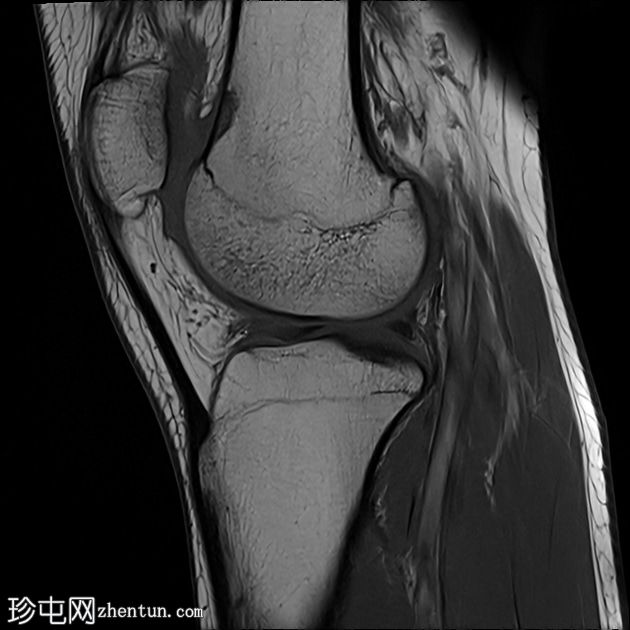

矢状位

T1加权像

内侧髌股韧带撕裂,伴外侧髌骨半脱位。

内侧髌骨缘可见骨髓水肿和一小块皮质撕脱碎片,内侧髌骨关节面存在全层软骨缺损。

外侧股骨髁轻度骨髓水肿。

内侧副韧带和外侧副韧带II级损伤。

膝关节积液

这些影像学表现是滑车发育不良的典型特征,滑车发育不良是髌骨不稳定的最常见病因,尤其是复发性髌骨外侧脱位。